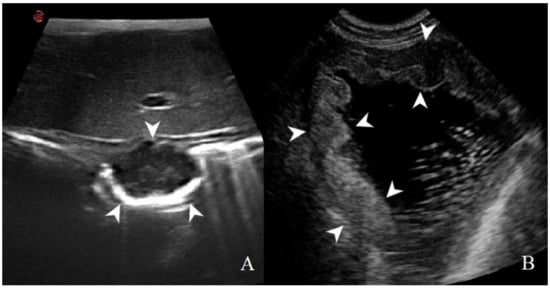

3.2. Analysis of B-Mode Examination

3.3. Analysis of CEUS Examination